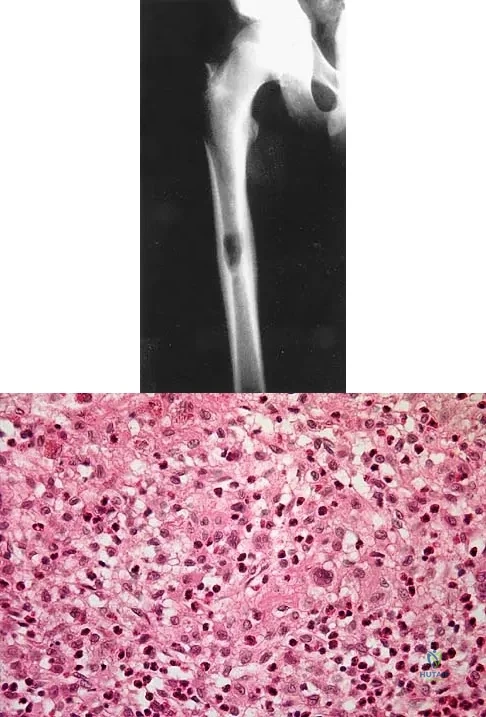

A previously healthy 13-year-old girl has had thigh pain for the past 3 weeks. The radiograph shown in Figure 47a reveals a lesion in the right femur. A bone scan and CT scan of the chest show no evidence of other lesions. A biopsy specimen is shown in Figure 47b. What is the most likely diagnosis?